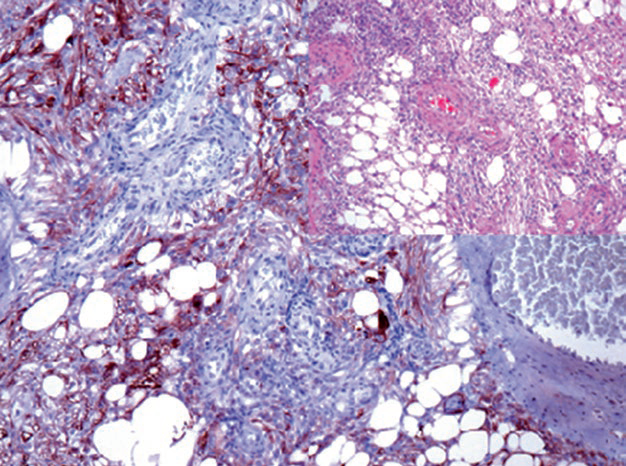

图1. 肾脏血管平滑肌脂肪瘤中,血管周围上皮样细胞表达HMB45。